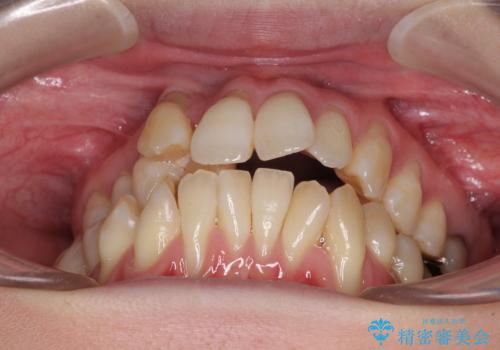

- 前歯のデコボコと唇の閉じにくさを気にして来院された患者様です。

上顎骨よりも下顎骨の幅が広く、更には下顎骨が左側に変位していたため、より良い咬み合わせを達成することを目的として、急速拡大装置を用いて上顎骨を拡大することとしました。

デコボコが強い上に、口元の突出感も気にしていたため、上下左右の小臼歯4本を抜歯して、ワイヤー装置にて矯正治療を行うこととしました。

歯根露出が顕著であったため、歯の移動は早く、スムーズに治療を終えられるかと思いましたが、歯槽骨が硬く、治療は長期間に及びました。

過剰に力をかけ続ける事態となり、一部の歯では変色したり、神経が失活したりとトラブルが続きました。

それでも当初とは比べものにならないほど、綺麗な歯列に仕上げることができました。